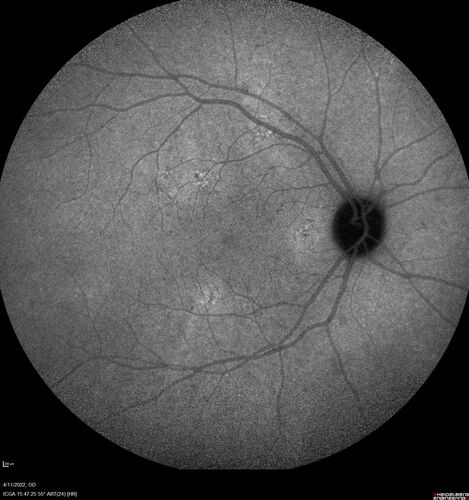

Acute Syphilitic Posterior Placoid Chorioretinitis

40 year old man About 10 days ago the patient woke up with a dark circle in the middle of the left eye that blocks his vision.  He thought it might be from fatigue.  The month of March was very stressful.  After a few days the spot in the left eye got darker and he could not drive at night.  During the last week while not going to work and sleeping more his vision is better but not normal.  He has never had vision loss in the past.

VA OD: sc20/16 NscJ1+VA OS: sc20/32+2 NscJ4

IOP: TP: OD:12 OS:12